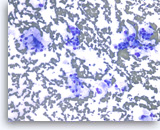

Ductal adenocarcinoma #1,

Pancreas FNA, Direct Smear.

The aspirates show single and clusters of malignant epithelial cells. The clusters are three-dimensional with overlapped nuclei. A few histiocytes are seen in the background.

20X

Ductal adenocarcinoma #1,

Pancreas FNA, Direct Smear.

The aspirates show single and clusters of malignant epithelial cells. The clusters are three-dimensional with overlapped nuclei. A few histiocytes are seen in the background.

20X